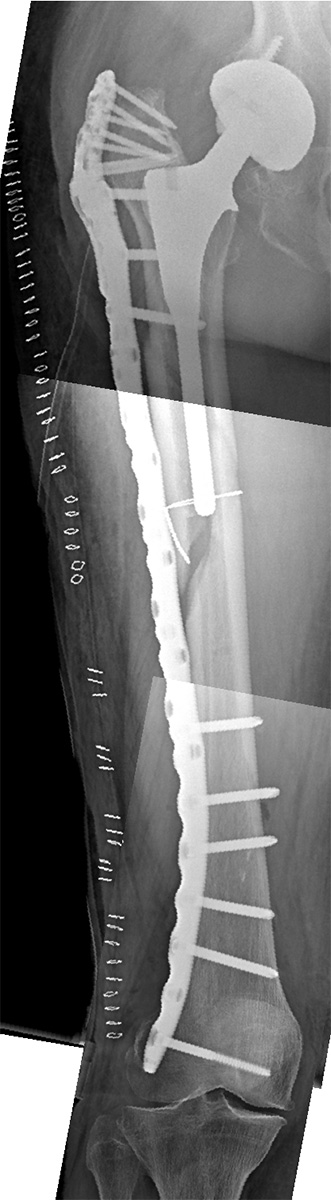

This 82-years-old male patient sustained a Vancouver B1 simple non-displaced periprosthetic fracture of right non-cemented THR after a low energy fall.

The fracture was firstly reduced by a minimally invasive approach and a cerclage wire (white arrows). The patient was placed in supine position on a traction table. The fracture was fixed with a 15 holes proximal femur periprosthetic NCB plate (PF PP) adding the trochanter plate to maximize fixation where the bone stock in the proximal fragment is: the greater trochanter. The plate was bent distally to protect the fragility of the supracondylar region: a cancellous screw is driven towards the medial condyle (in polyaxial mode) to prevent future fractures in the distal metaphysis of the femur. The external jig was used to place the screws in the shaft percutaneously, except the two most distal holes because of the the bending done on the plate.

In the one and 12 months follow-up X-rays, the fracture shows no displacement with no screw loosening, although the fracture was not yet healed. The patient did not feel pain at all.

In the 18 months follow-up X-rays, the fracture heals uneventfully with indirect bone healing due to the relative stability of the construction.